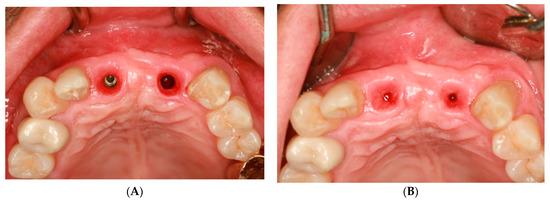

Prosthetic Management of Peri-Implant Mucositis via CRD Optimization: A Split-Mouth Case Report

Background: Subcrestally placed implants (SPIs) present advantages for bone preservation and soft tissue support but pose challenges in maintaining peri-implant soft tissue health. This case explores the role of Crest to Restoration Distance (CRD) in the development and resolution of peri-implant mucositis. Case [...] Read more.

Background: Subcrestally placed implants (SPIs) present advantages for bone preservation and soft tissue support but pose challenges in maintaining peri-implant soft tissue health. This case explores the role of Crest to Restoration Distance (CRD) in the development and resolution of peri-implant mucositis. Case Presentation: A 57-year-old woman received two SPIs—one in the upper left and one in the lower right first molar region. Despite similar implant systems and prosthetic protocols, the upper left implant developed mucositis, characterized by bleeding on probing and discomfort, while the lower right implant remained stable. Three-dimensional analysis using cone-beam computed tomography (CBCT) revealed excessive CRD at the affected site. Results: After prosthodontic revision to reduce the CRD, clinical signs of mucositis resolved, with probing depths reduced to less than 1 mm and no bleeding on probing. The control site remained healthy throughout the observation period. Practical Implications: This case highlights CRD as a modifiable prosthetic factor influencing soft tissue stability. A three-zone model—comprising the sulcus, transitional zone (TZ), and subcrestal zone (SZ)—is introduced to provide a biologically grounded framework for understanding soft tissue adaptation around SPIs. Full article